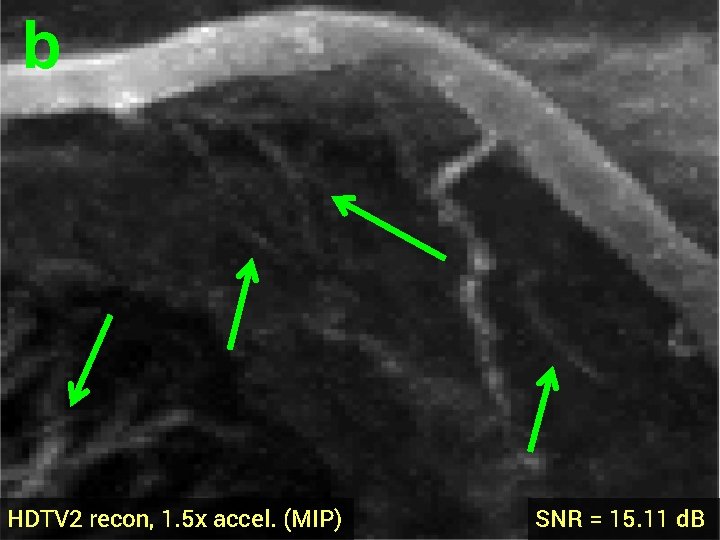

3 -D Compressed Sensing MRA § 512 x 76 voxel MRA dataset obtained from physiobank (see ref. [6]) § Simulated single coil acquisition § Retroactively undersampled at 1. 5 -fold acceleration § Random Gaussian sampling of k-space § 5 d. B additive Gaussian noise § Optimized regularization parameter MIP of original MRA dataset

b a HDTV 2 recon, 1. 5 x accel. (MIP) SNR = 15. 11 d. B

b HDTV 2 recon, 1. 5 x accel. (MIP) SNR = 15. 11 d. B

3 -D Quantitative Results Table 3: 3 -D Comparisons. SNR (in d. B) of recovered images with optimal reg. param. Denoising Cell 1 Cell 2 Deblurring Cell 1 CS-MRI Cell 2 Cell 3 Angio, acc=5 Angio, acc=1. 5 Cardiac TV 17. 12 16. 25 19. 02 16. 43 14. 50 13. 87 14. 53 18. 37 HDTV 2 17. 25 16. 70 19. 15 16. 60 14. 87 14. 23 15. 11 18. 56 HDTV 3 17. 68 17. 14 19. 73 17. 43 15. 23 14. 01 14. 70 18. 50 § HDTV outperforms TV in all experiments § HDTV 3 better for denoising and deblurring § HDTV 2 better for CS-MRI